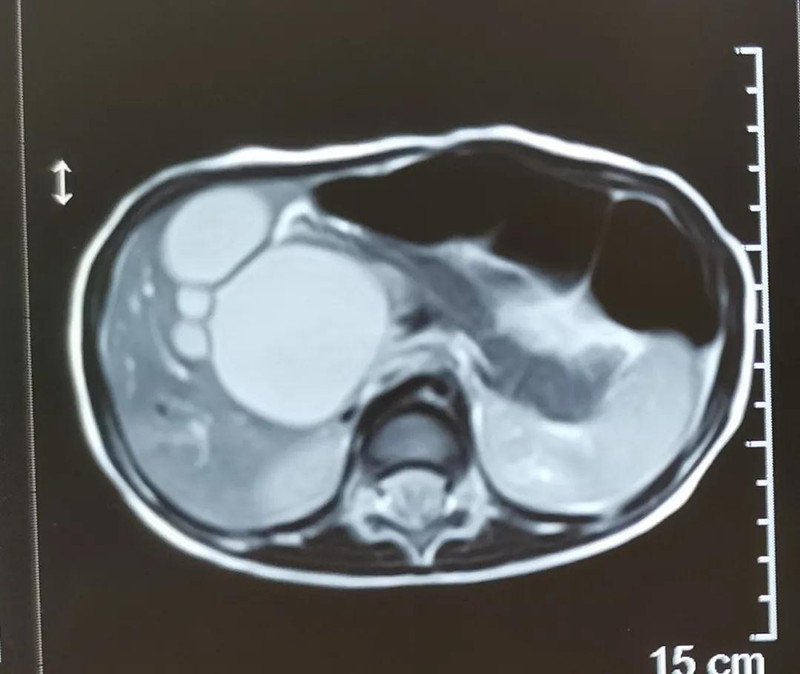

最近半个月,长春市26个月女宝馨馨(化名)脸色不好,全身发黄严重,还伴随发烧。9月23日,馨馨被家人带到蜜桃视频 诊治。经检查,馨馨全身发黄是因为患有黄疸,而黄疸的出现是因为胆总管发生病变,“胆总管呈现囊性扩张,下边出口被堵住,胆汁进不到肠腔里,导致孩子出现黄疸、肝功不好、白土便症状。而且胆总管胀大后,还有癌变的风险,”普外、新生儿外科主任崔钊说,馨馨需要尽快手术。为了减少损伤,崔钊主任团队制定的方案是单孔腹腔镜下胆总管囊肿根治手术。